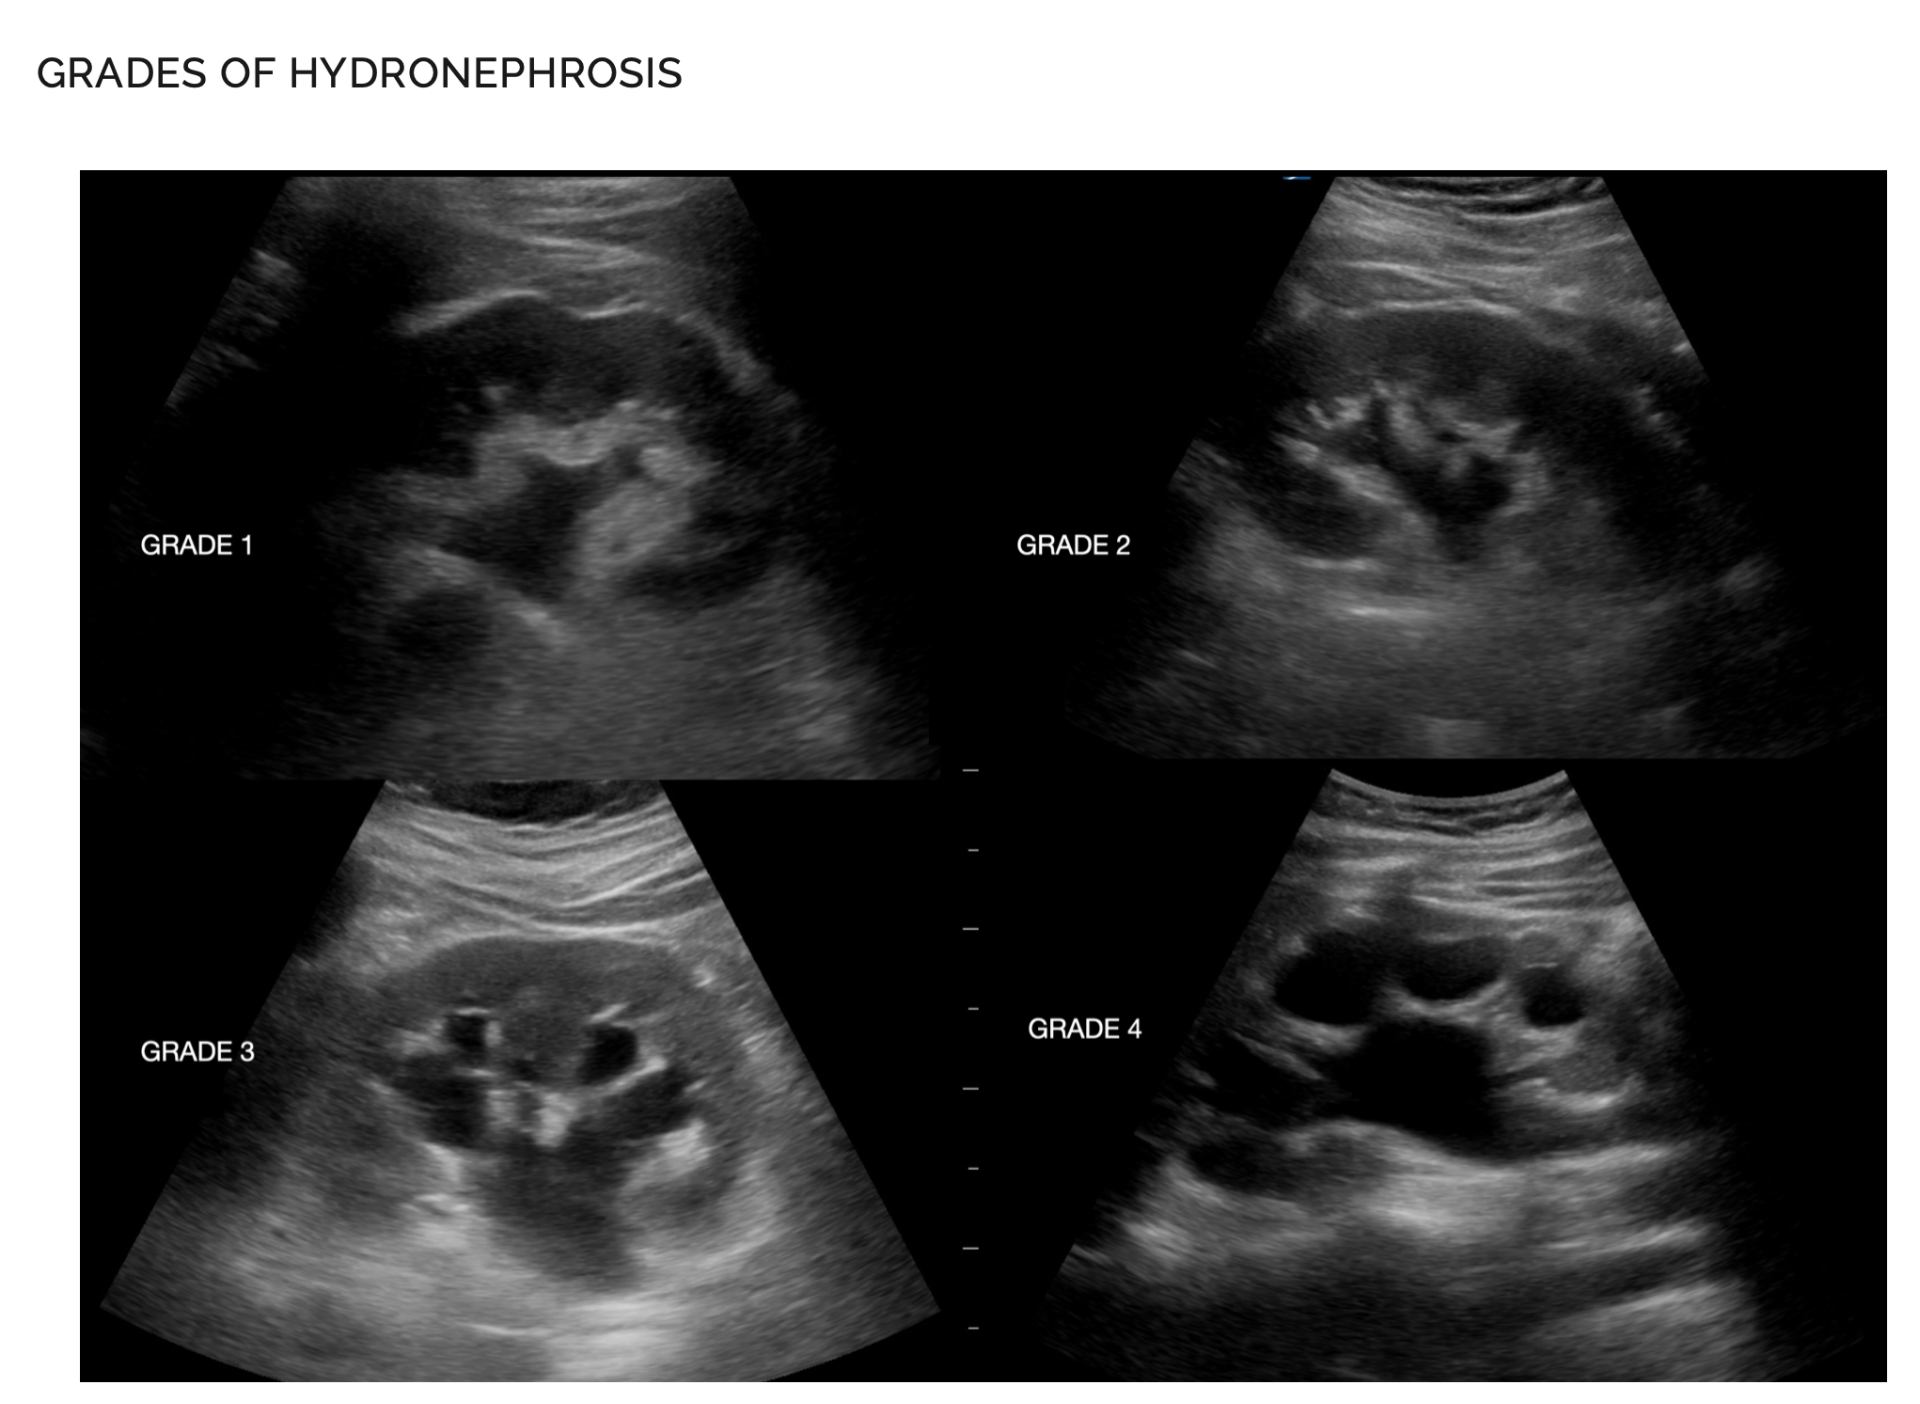

Grades of hydronephrosis: Grade 1: dilated pelvis and ureter only; Grade 2: + dilated calyces, but not clubbed; Grade 3: + clubbed cayces but normal cortical thickness >1cm; Grade 4: + thin cortex